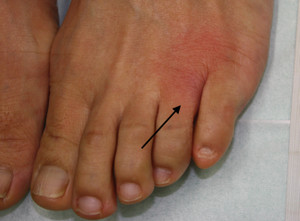

師長の足に水虫が・・・![]()

でも顕微鏡検査では、水虫菌(白癬菌)はいません![]()

これは、水虫ではないのです。汗疱といいます。いわば、汗疹(あせも)

の一種です![]()

これからの湿度

と気温

が高くなる季節は、この皮膚炎が多くなります。自称水虫の方の1−2割がこれですね![]()

大抵は、すでに市販の水虫薬を塗って悪化させておられます![]()

市販薬を塗ってもどんどん悪化する場合は要注意です